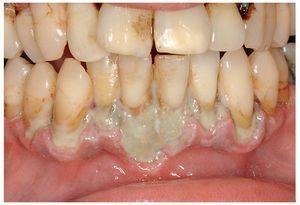

El VHS 1 es el responsable de más del 90% de las enfermedades de la mucosa oral causadas por el VHS. Un porcentaje superior al 85% de la población mundial es seropositivo para el VHS 1. La primoinfección suele producirse durante la infancia, dando lugar a un cuadro clínico que muchas veces pasa desapercibido. Sin embargo, en otros casos, tras un período de latencia de 3 a 10 días después del contagio se desarrolla un cuadro sistémico grave con fiebre alta, dolor de garganta, adenopatías cervicales y gingivoestomatitis herpética aguda. En los labios, alrededor de la boca, en la mucosa bucal y gingival y también en la orofaringe aparecen numerosas vesículas que se transforman en erosiones extensas y úlceras superficiales asociadas a dolor intenso al comer y al hablar. Estas vesículas pueden aparecer en la mucosa queratinizada y también en la mucosa no queratinizada (fig. 1). La enfermedad tiene una duración aproximada de 2 a 3 semanas, lo que en determinados casos provoca una pérdida de peso importante, dado que durante este período los pacientes a menudo sólo pueden ingerir líquidos. El tratamiento es sintomático. Además de analgésicos sistémicos y de un colutorio bucal con acción desinfectante y acción anestésica local, a menudo se prescribe un antibiótico si existe una sobreinfección. En pacientes inmunodeprimidos está indicado un tratamiento antiviral sistémico con aciclovir. Por lo demás, se trata de una enfermedad autolimitada.

Figura 1. Gingivoestomatitis herpética como primera manifestación de una infección por el virus del herpes simple tipo 1.